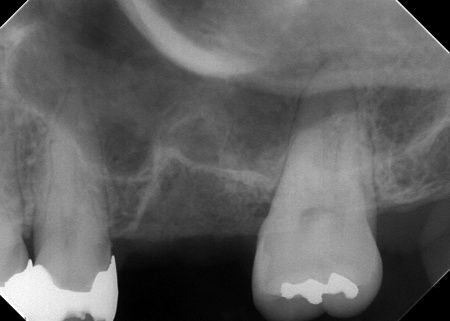

さらに、左上奥歯(第1大臼歯)は温存が難しい状態でした。

③温存が難しい左上奥歯(第1大臼歯)は抜き、骨を再生させる処置「GBR(骨造成)」を行ったのち、人工歯根を埋め込む「インプラント治療」により噛む機能を回復させます。

左上奥歯1本は抜き、GBRで骨を再生させたのち、インプラントを埋入します。

インプラントに装着する人工歯の素材には、自費診療の白いセラミックを選択しました。